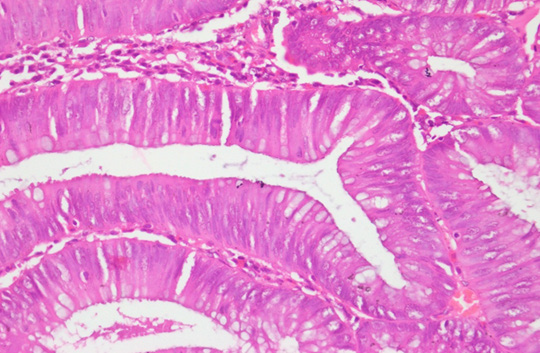

Photomicrograph

Figure 12: Photomicrograph of Adenomatous polyp Ki-67 expression: Positive (Case No: 48, IHC X 40x).